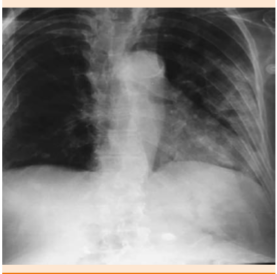

La paciente acudió al servicio de Urgencias el 29 de octubre de 2014 por padecer adinamia, alza térmica no cuantificada, calosfríos de 48 horas de evolución. Exploración física: presión arterial 110/60 mmHg, frecuencia cardiaca 90 lpm, frecuencia respiratoria 22 rpm, temperatura 38.2ºC. Somnolencia, estertores subcrepitantes en hemitórax izquierdo en ambas fases de la respiración y submatidez ipsilateral. Los estudios de laboratorios al ingreso arrojaron lo siguiente: Hg 12.0 g/dL, HCTO 38%, VCM 91 fl, HCM 28.8 pg, plaquetas 299,000 μL, leucocitos 14,900 μL, neutrófilos 93%, bandas 3%, linfocitos 1%, urocultivo con Escherichia coli. Recibió tratamiento específico; sin embargo, durante su internamiento tuvo evolución tórpida con signos vitales de presión arterial 80/50 mmHg, frecuencia cardiaca 98, frecuencia respiratoria 21, por lo que se ingresó a terapia intensiva con diagnóstico de neumonía nosocomial SMART COP 6 (riesgo alto) y choque séptico (Figura 1).